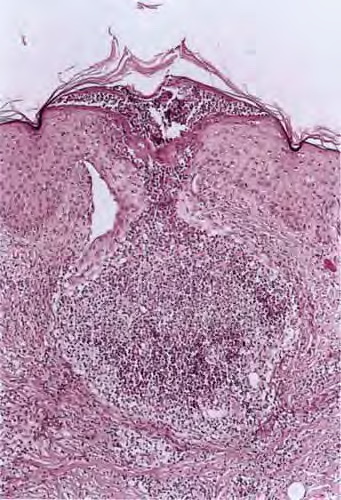

Folliculitis with subcorneal pustule formation = التهاب أجربة شعرية +بثرة تحت القرنية